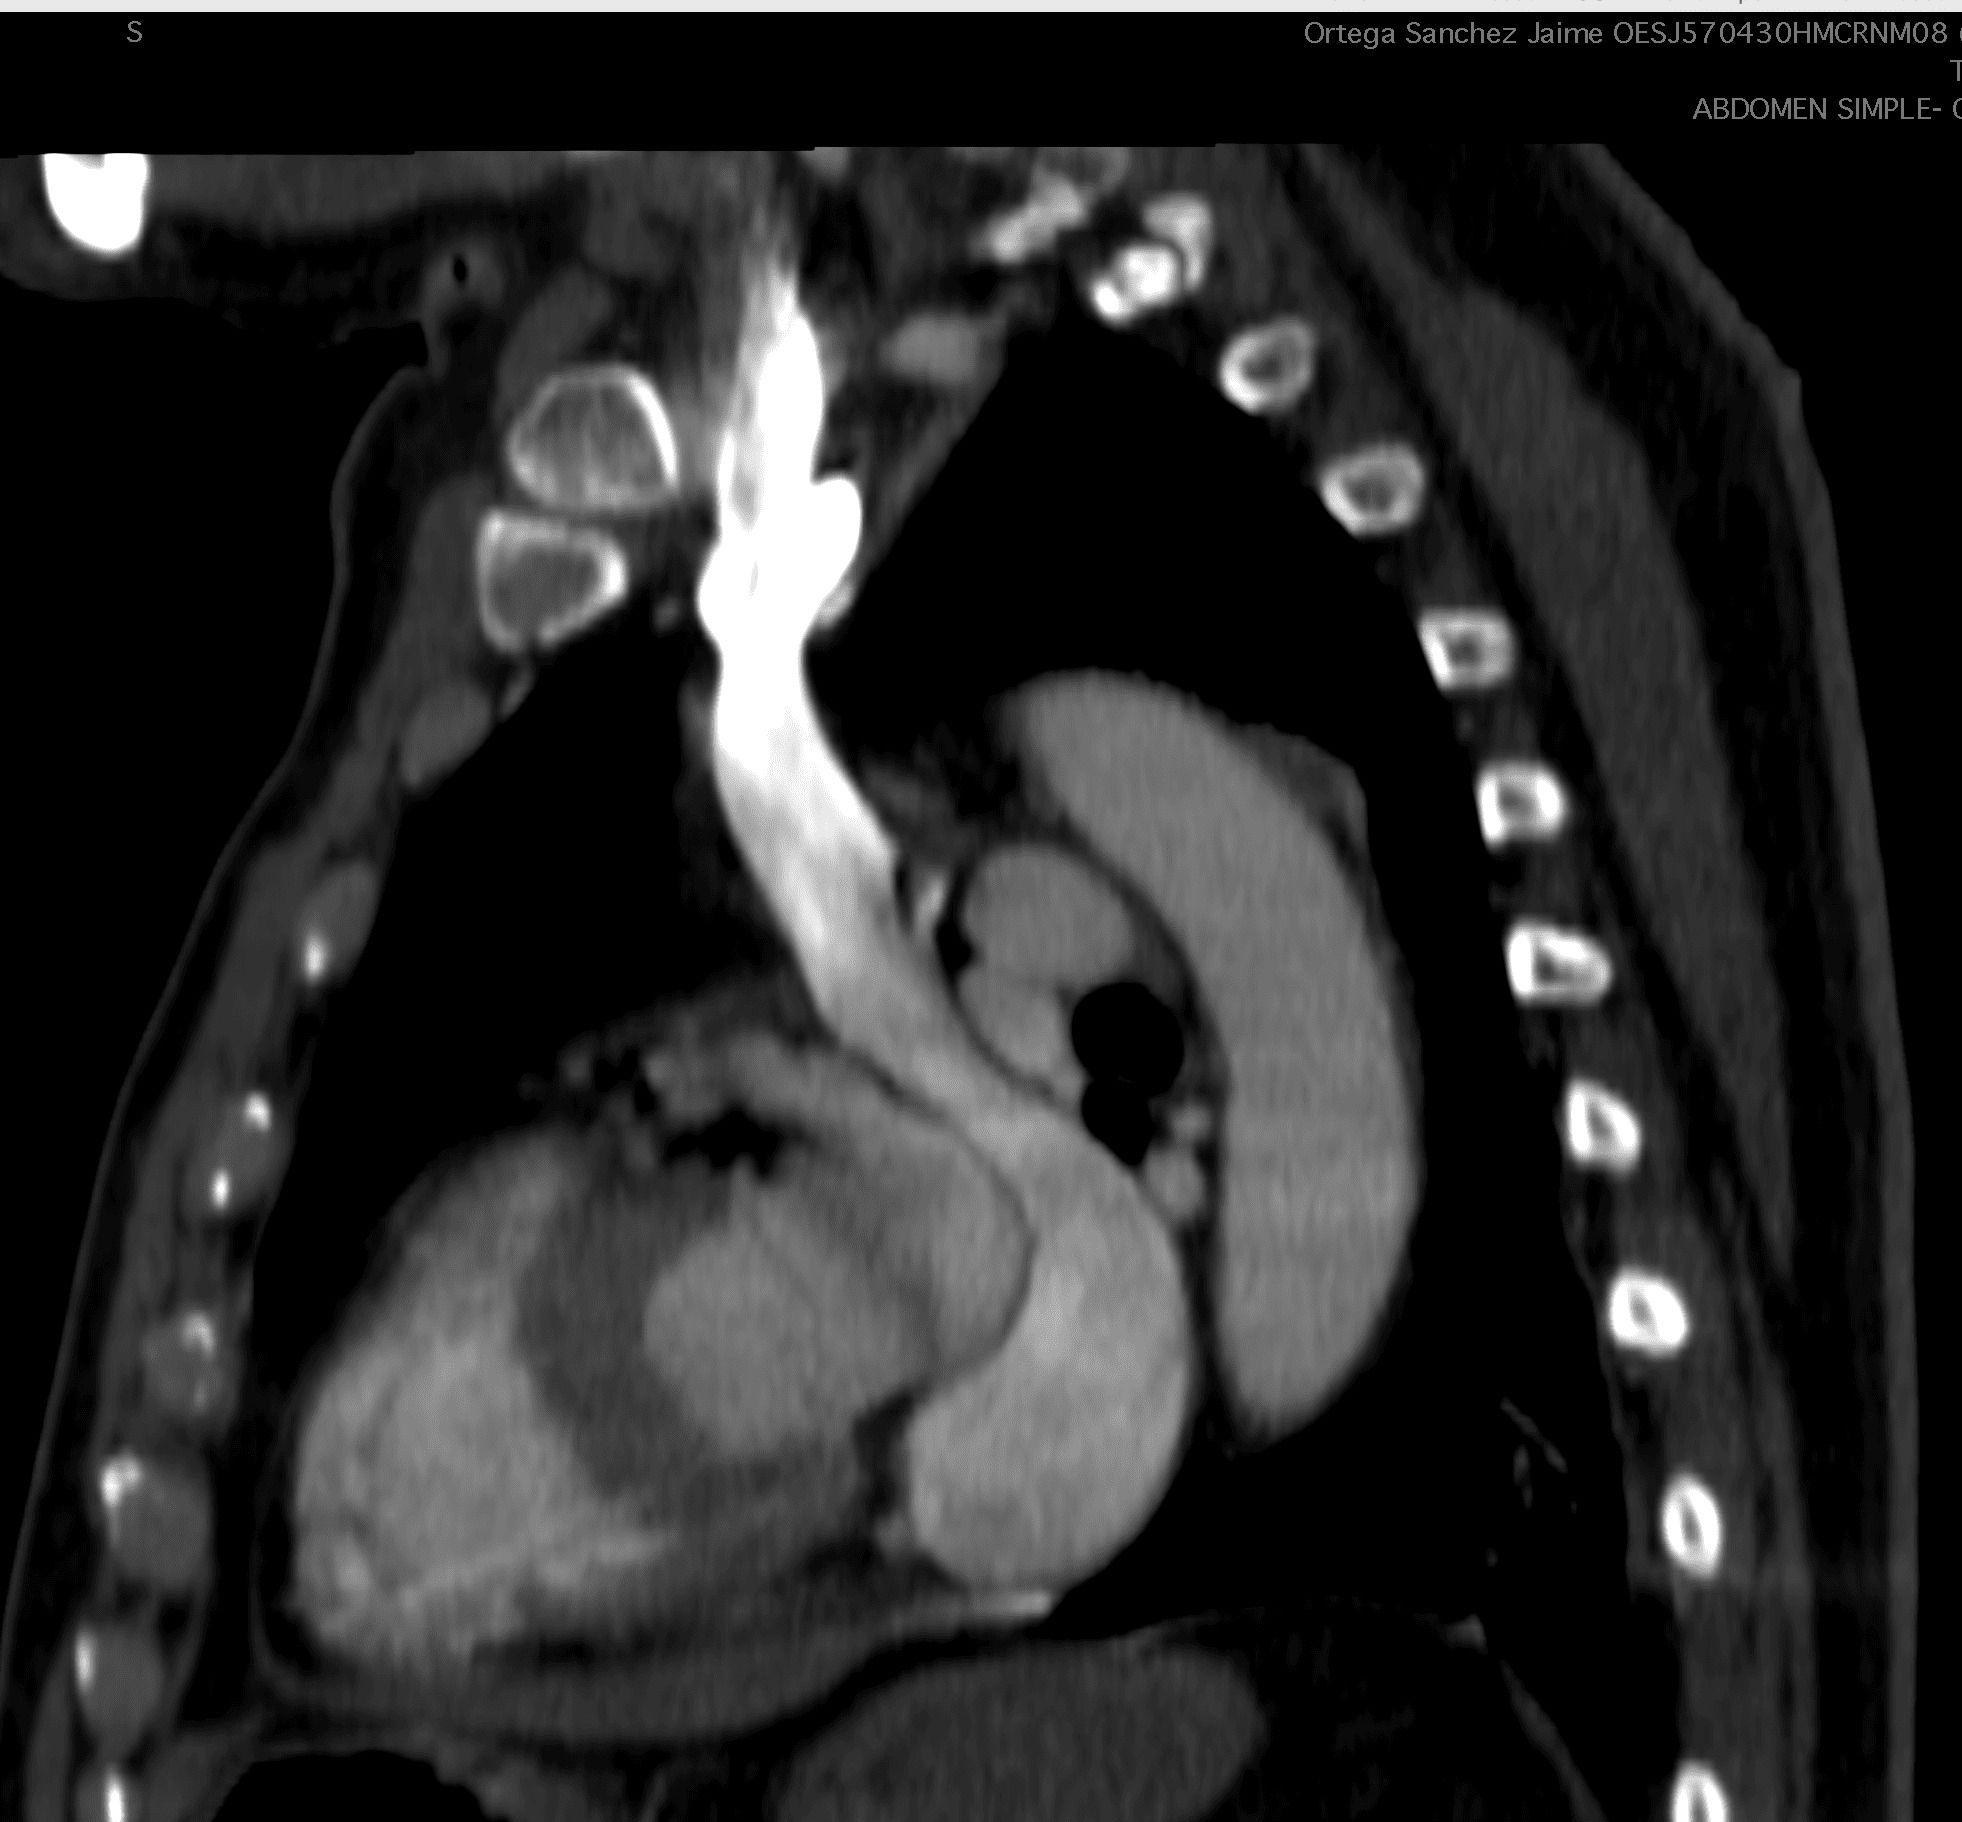

During the procedure in the cardiac catheterisation laboratory, difficulties were encountered in advancing the guidewire towards the subclavian vein. Consequently, bilateral subclavian vein angiography was performed, which revealed a persistent left superior vena cava with anomalous drainage into the coronary sinus. The procedure was therefore deferred.

A cardiac CT angiogram confirmed the diagnosis. The cardiothoracic surgery team was subsequently consulted, and an epicardial pacemaker was successfully implanted via a subxiphoid approach in DDDR mode.